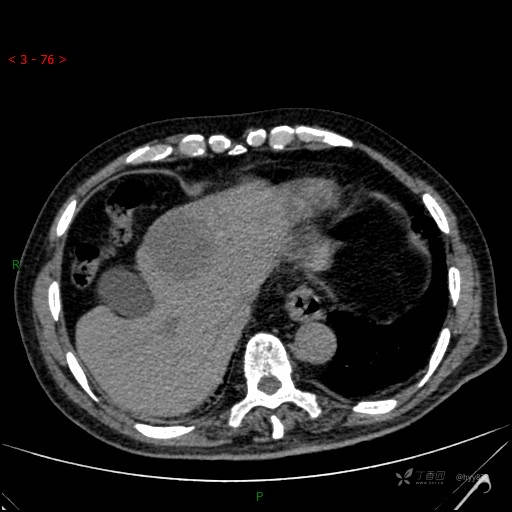

肝脏CT平扫

img